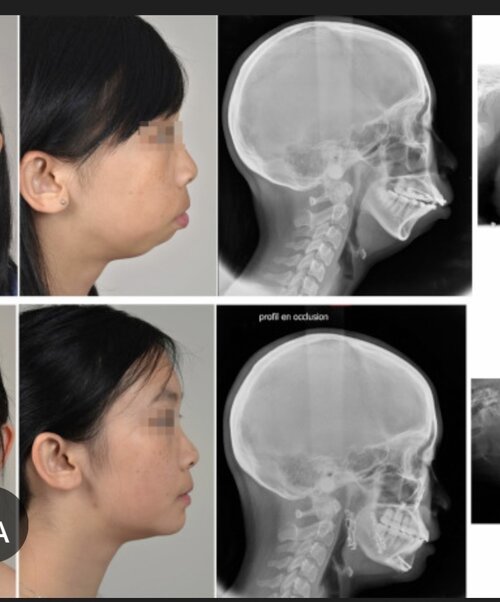

View attachment 4456968can you please stop frowning? you look like shit